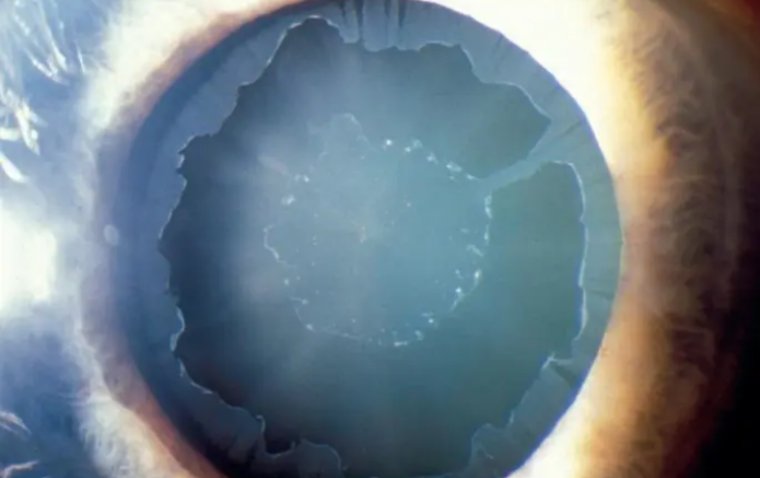

Diagnosis of pseudoexfoliation syndrome (PEX) usually involves a comprehensive eye examination conducted by an ophthalmologist. The most characteristic symptom of PEX is the presence of white, flaky material on the lens and the structures of the front part of the eye. This material is often observed during a slit-lamp examination - a test that uses a special microscope and light source to examine different parts of the eye.

In addition to the white deposits, patients with PEX may exhibit symptoms related to other eye conditions, such as glaucoma or cataracts, which are frequently associated with PEX. Increased intraocular pressure, a key indicator of glaucoma, may be present, while signs of cataracts include clouding of the lens and blurred vision.

Pseudoexfoliation syndrome (PEX) is associated with a number of eye conditions and potential complications that can significantly affect ocular health. It is most notably linked with pseudoexfoliation glaucoma, which is a type of secondary open-angle glaucoma. The white, flaky material characteristic of PEX can block the eye's drainage system, leading to increased intraocular pressure, a hallmark of glaucoma. This can cause optic nerve damage and, if left untreated, vision loss.

Additionally, PEX is often associated with cataracts. The presence of pseudoexfoliative material can interfere with the normal functioning of the lens, causing it to become cloudy over time. Cataracts in PEX patients are known to progress more rapidly and can make cataract surgery more challenging due to weakened zonular fibers, which secure the lens in place.